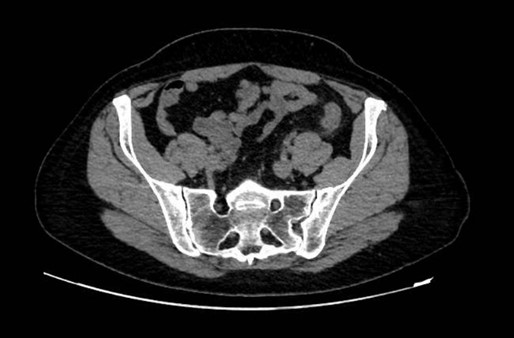

Ante la sospecha de cólico nefrítico complicado, se realiza ecografía abdominal, que muestra en fosa ilíaca izquierda, un foco ecogénico con sombra acústica posterior y engrosamiento de la pared intestinal de 6 mm. Se confirma mediante tomografía computarizada la presencia de divertículos en el colon izquierdo, con un divertículo engrosado entre el colon descendente y sigma, y discretos cambios inflamatorios pericólicos. Con mínimo líquido en la gotiera adyacente, sin colecciones ni burbujas de gas extraluminal.

Este caso subraya la importancia de una anamnesis completa y exploración física, que aunque no definitivas, ayudan a orientar el diagnóstico diferencial. Aunque diagnósticos comunes como el cólico nefrítico son frecuentes, es crucial no descartar otras patologías que podrían complicarse sin tratamiento adecuado. La ecografía, como herramienta inicial, permitió detectar signos de diverticulitis aguda no complicada, orientando el diagnóstico y tratamiento. Complementada por la tomografía computarizada, la ecografía demostró ser útil en el dolor abdominal localizado, destacando la importancia de un diagnóstico integral y el uso adecuado de herramientas disponibles.